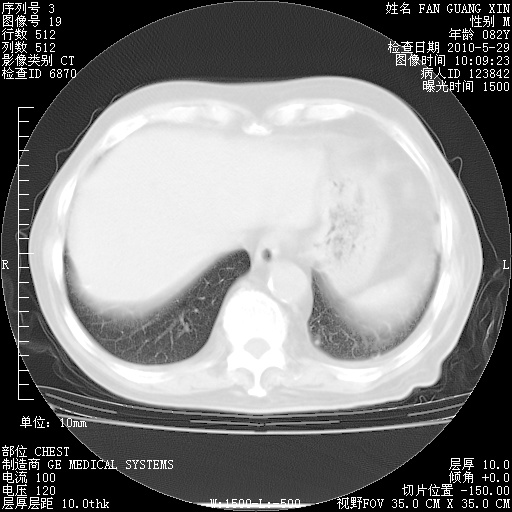

再治疗10天后的肺部CT 纵膈窗

阅读此次胸部CT,肺间质渗出性改变较入院时有吸收。目前从体温、白细胞、中性分叶明显增高,肯定存在细菌感染(发生医院感染哦,若无消化道及泌尿系统等感染的依据,肺部感染可能大)。若你院头孢哌酮舒巴坦钠耐药率较高,同意你的方案,若48小时体温仍高,可考虑使用碳青霉稀类抗菌药物,同时可予超声雾化、注意滴数时加大液体量。白蛋白33.30g/L较低哦,需加强营养等支持治疗。